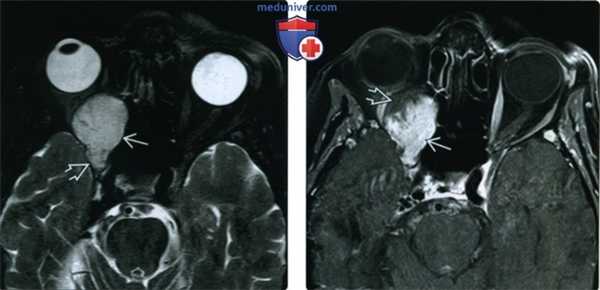

(Слева) При MPT Т2ВИ FS в аксиальной проекции в правой глазнице определяется крупное гиперинтенсивное несколько дольчатое объемное образование, заполняющее верхушку глазницы. Это медленно растущее образование вызвало расширение верхней глазничной щели.

(Справа) При МРТ Т1ВИ FS в аксиальной проекции наблюдается неполное, но интенсивное контрастирование крупной кавернозной мальформации глазницы, простирающейся в верхушку глазницы. Неконтрастируемые участки, вероятно, будут заполнены контрастом на поздних томограммах.